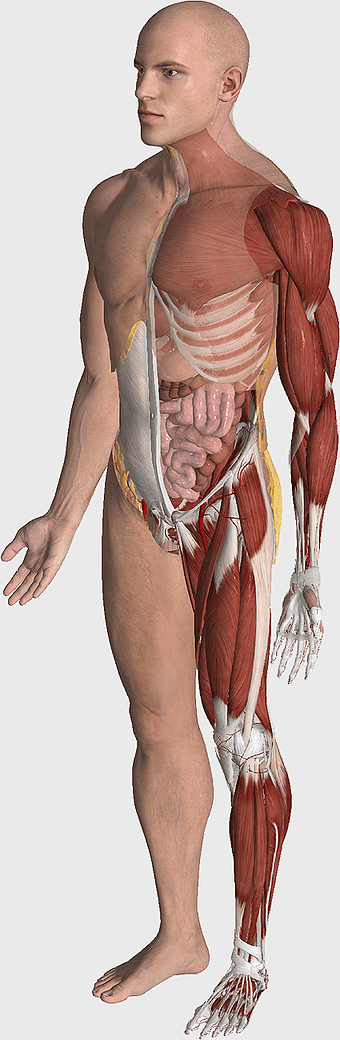

human anatomy illustration, male body diagram, human limb structure, surface anatomy chart, human skeletal outline, full-body medical sketch, human joint depiction -

1024x697px

muscular system illustration, human anatomy diagram, fitness professional figure, skeletal muscle structure, muscular development, human body musculature, anatomical study -

614x1024px

human muscular system illustration, muscle anatomy human body, fitness professional bodybuilder, human back and abdomen muscles, anatomical muscle structure, human skeletal muscle system, detailed human muscle chart -

1024x1024px